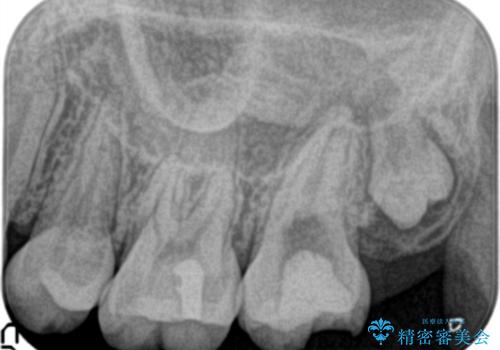

- 他院にて奥歯の治療をしても痛みが引かずに、ラバーダムの存在を知り、無菌的な治療を行える病院を探して当院を受診されました。

根管治療~フルジルコニアクラウンにて修復しております。

治療前には打診、圧痛がありましたが治療後には症状が消失し、3ヶ月後のレントゲンでも透過像の縮小を認めています。

治療介入時、根管内部にはカリエスや異物が存在する状態でしたが適切な処置を行うことで症状を改善することができました。